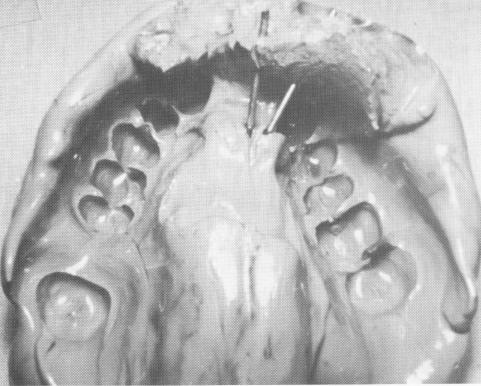

To make the bone impression, infiltration anesthesia was given labially and palatally. An incision was made along the edentulous ridge crest from the mesial surface of the left central incisor to the mesial surface of the right cuspid. The incision became continuous labially and lingually with the gingival tissue that was attached at the neck lines of neighboring teeth. The tissues were reflected to expose a good portion of the labial and palatal plate of bone (Fig. 12-86) .

1 Pins transfixed through maxillary bone prior to elastic impression